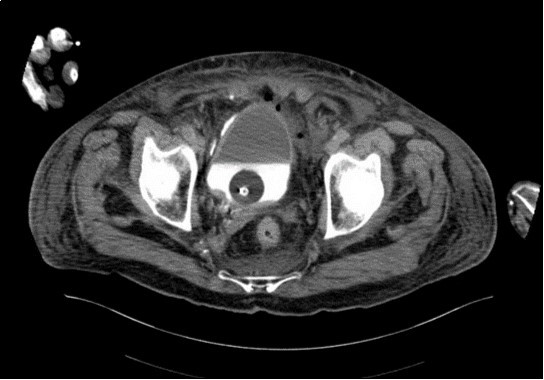

His irrigation circuit-chart showed he had received 10 litres Normal Saline via the afferent limb, but only 3 litres recorded at the efferent limb. It was suspected the catheter was adjacent to a vascular-cystic interface, however an urgent contrast CT revealed the irrigating catheter perforating the bladder, being situated in the abdominal cavity (see 3 images). His arterial blood-gas analysis demonstrated the expected normal anion-gap academia, however his Strong Ion Difference calculations, sodium-chloride difference of 13 and a normal albumin level, perfectly demonstrated the expected calculated BE of -13. The catheter was withdrawn, and the patient made a full recovery.

An urgent CT abdomen revealed a bladder perforation with the tip of the irrigating catheter situated in the abdominal cavity (Figure 1, Figure 2, Figure 3a,Figure 3b). This was most likely due to over-insertion of the 3-way catheter due to the extra force required because of the benign prostatic hypertrophy. He had therefore been receiving normal saline as ‘peritoneal dialysis’ with normal saline since insertion of the catheter. The catheter was withdrawn, and the patient made a full recovery.

Figure 3a.horizontal plane CT image 2